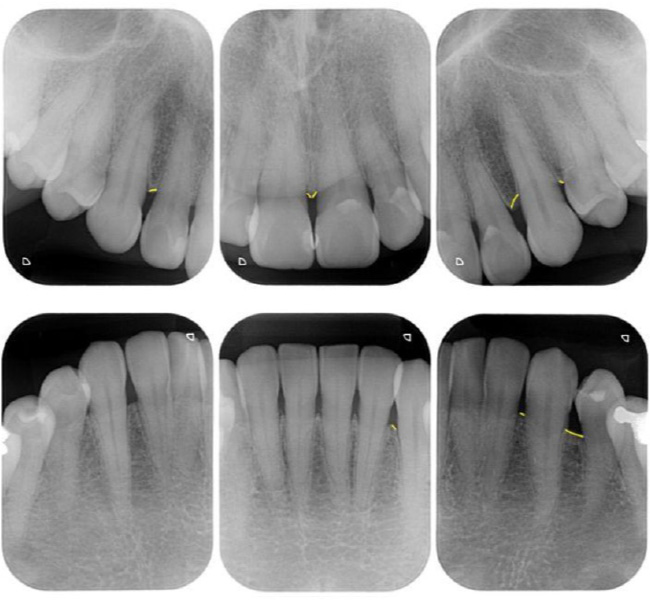

治療前

| 治療内容 | 全顎治療:歯周病治療、根管治療、 歯肉弁剥離掻爬術(フラップ手術)、 セラミック治療、ダイレクトボンディング |